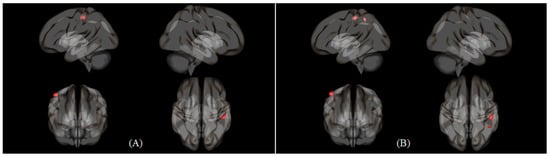

| Nasal > Oral | Cerebellum 6 (L) | Cerebellum 8 (R) | 240 | 5.538 | 4.771 | 36 | −58 | −44 |

| Inferior parietal gyrus (R) | Parietal operculum cortex (R) | 179 | 4.944 | 4.364 | 52 | −34 | 26 | |

| Postcentral gyrus (L) | 114 | 4.617 | 4.129 | −36 | −26 | 48 | ||

| Cerebellum 6 (R) | 115 | 4.241 | 3.847 | 24 | −54 | −24 | ||

| Inferior parietal gyrus (L) | Postcentral gyrus (L) | 239 | 4.927 | 4.352 | −34 | −28 | 48 | |

| Middle frontal gyrus (L) | Anterior cingulate gyrus | 146 | 4.571 | 4.095 | −2 | 14 | 32 | |

| Lateral occipital cortex, (superior division) (L) | 202 | 4.312 | 3.901 | −20 | −88 | 38 | ||

| Oral > Nasal | Inferior frontal gyrus, triangular part (L) | Postcentral gyrus (R) | 123 | 4.620 | 4.131 | 50 | −32 | 56 |

| Middle frontal gyrus (L) | Postcentral gyrus (R) | 215 | 4.449 | 4.004 | 50 | −30 | 54 | |